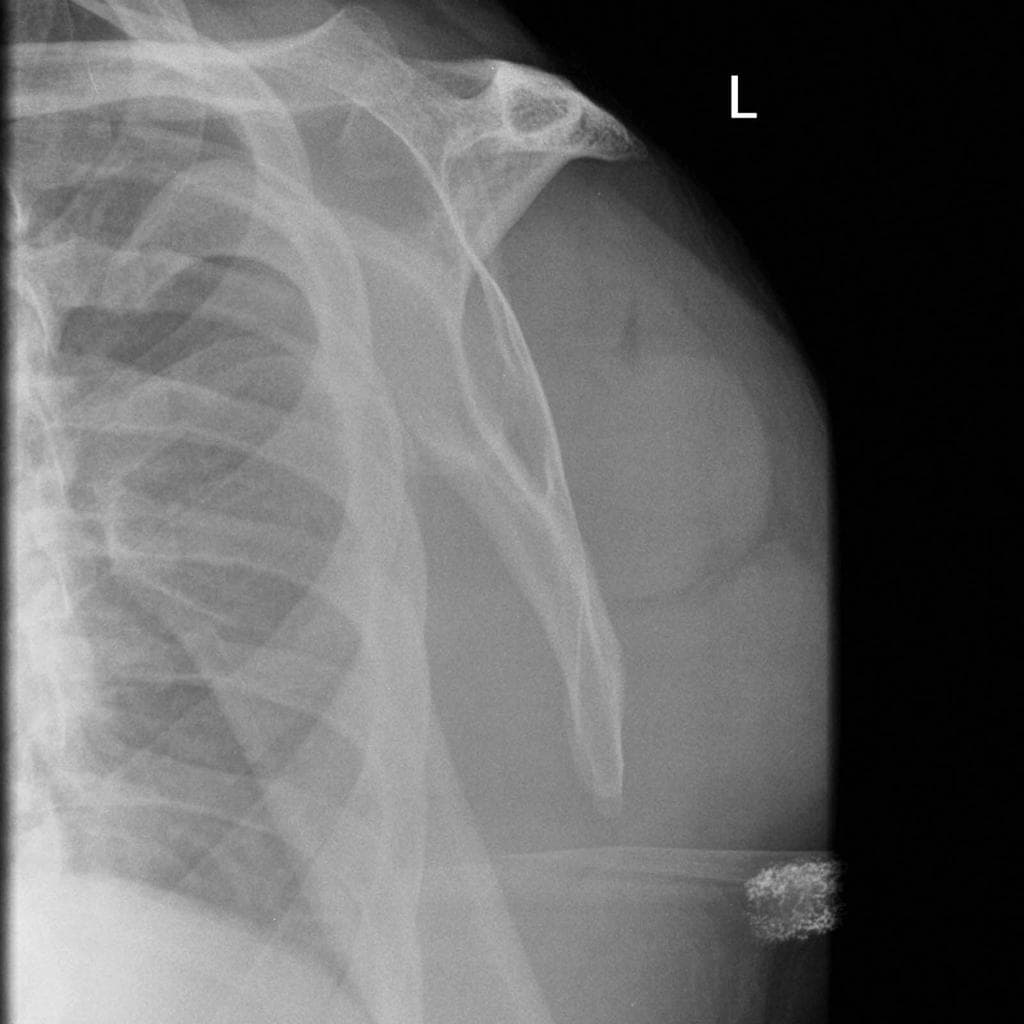

Trật khớp vai ra trước. Trục khớp ổ chảo - cánh tay bình thường. Không thấy trật khớp. THẢO LUẬN: Hình ảnh X-quang khớp vai phải cho thấy tình trạng trật khớp ra trước, đã được nắn chỉnh thành công.

- "Thế chụp nách hoặc thế chữ Y xương bả vai là cần thiết để xác định hướng trật khớp."

- "Luôn thực hiện chẩn đoán hình ảnh sau nắn chỉnh để xác nhận sự thẳng trục."

Trật khớp vai ra trước thường xảy ra sau khi ngã với cánh tay ở tư thế giang và xoay ngoài. Chỏm xương cánh tay bị di lệch ra trước, vào trong và thường là xuống dưới so với ổ chảo. Đánh giá X-quang có vai trò quan trọng không chỉ để chẩn đoán mà còn để xác định các tổn thương xương đi kèm có thể ảnh hưởng đến việc điều trị và độ vững của khớp.